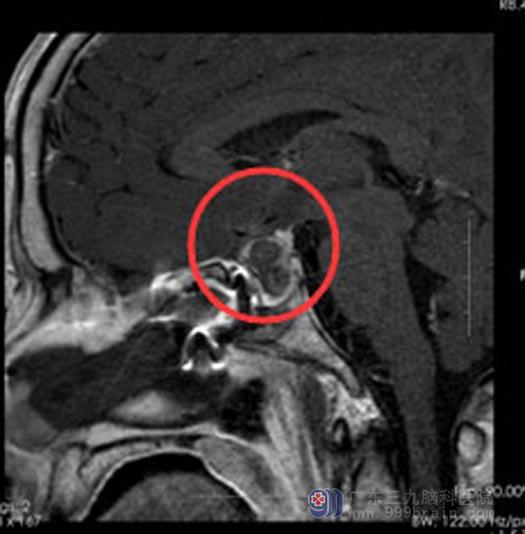

由垂体瘤诊疗中心鲁明主任主刀,内镜下经鼻蝶鞍区复发垂体瘤切除术,术中行导航定位,小心清除窦内粘膜,导航再次定位,磨除鞍下壁约1.6cm大小;钩刀“+字型”全层切开硬脑膜。见暗红色肿瘤包膜,切开包膜后肿瘤流出,肿瘤腔内留置数枚明胶海绵片,腹部脂肪填补术腔,修复鞍底,球囊支撑鞍底,手术过程顺利。

术后,徐先生恢复很快,几天便满意出院。

手术后